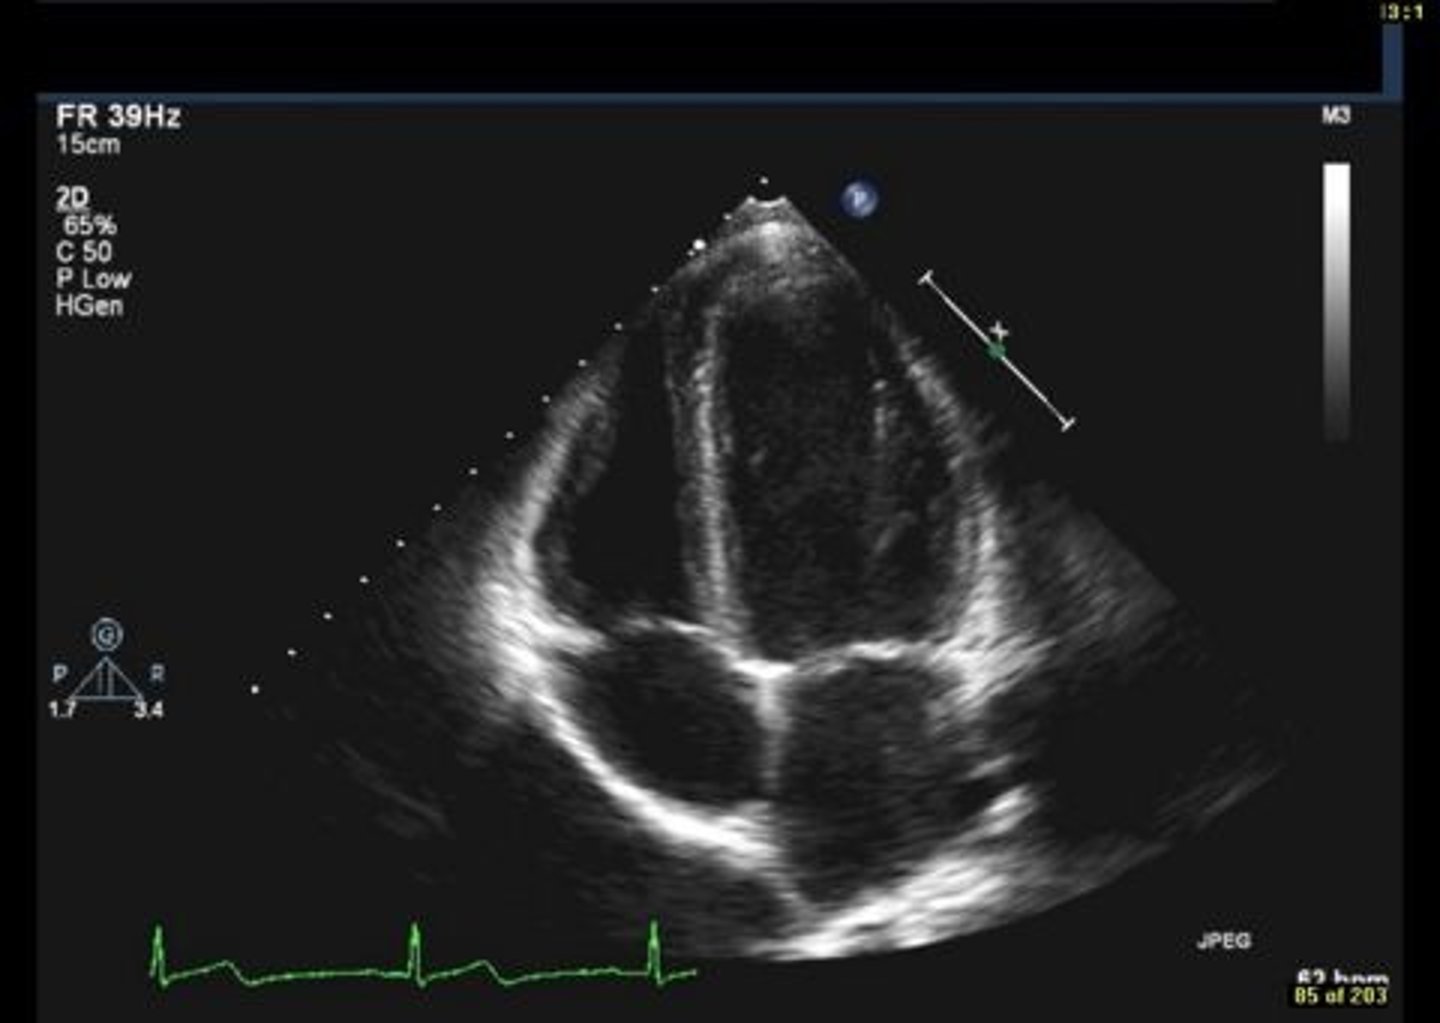

anterior mitral valve leaflet

top leaflet

posterior mitral valve leaflet

bottom leaflet